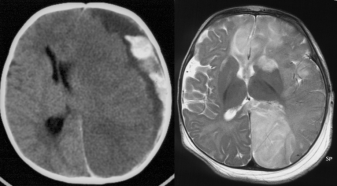

l’engagement paradoxal

appelé Kernohan’s notch, du nom de l’anatomo-pathologiste qui l’a décrit, il survient lorsqu’un facteur compressif (le plus souvent un hématome sous-dural) exerce une pression homogène sur l’encéphale, entraînant un déplacement avec compression du mésencéphale du côté opposé contre le bord libre de la tente du cervelet

il provoque donc une paralysie homolatérale à la compression (d’où le paradoxe).